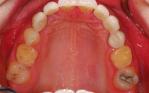

Orthodontic closure of the front gap and replacement of the loose baby teeth with some permanent implant crowns and bridgework.

Before